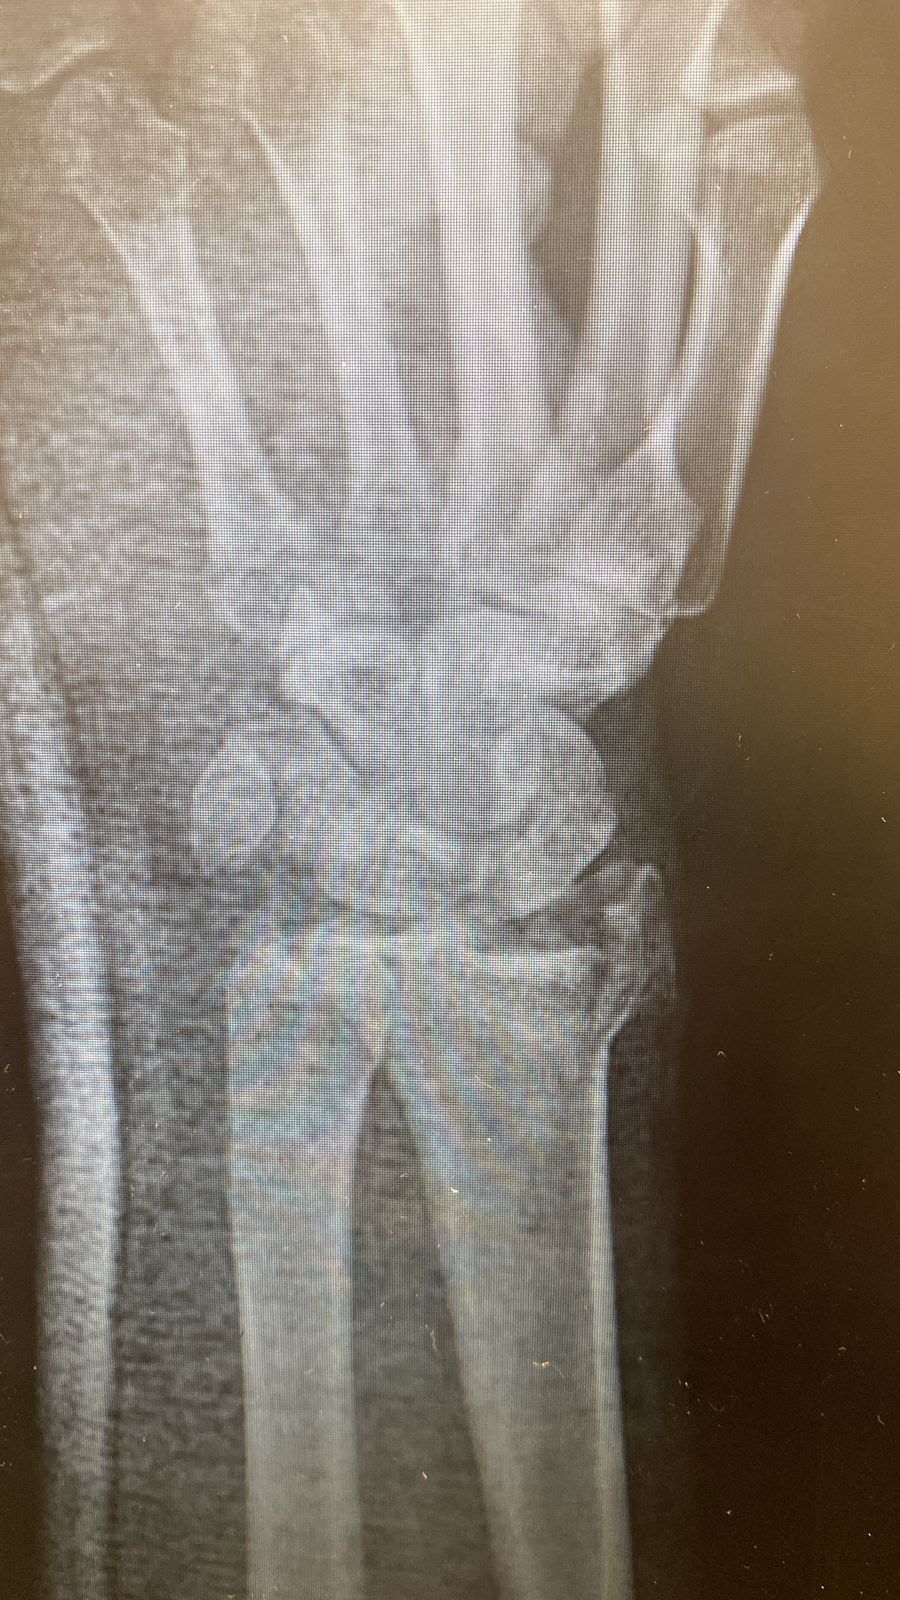

A radiografia de punho será crucial na avaliação inicial do paciente, sendo necessário as incidências póstero-anterior, perfil e oblíqua. Diversos parâmetros serão utilizados pelo cirurgião de mão para analisar a gravidade da fratura, sendo a radiografia do membro contralateral necessária em algumas situações. Da mesma forma, a

Parâmetros básicos radiológicos utilizados nas radiografias. A - Tilt volar, B - Inclinação radial, C - Variância ulnar.

Parâmetros radiográficos na incidência em perfil.